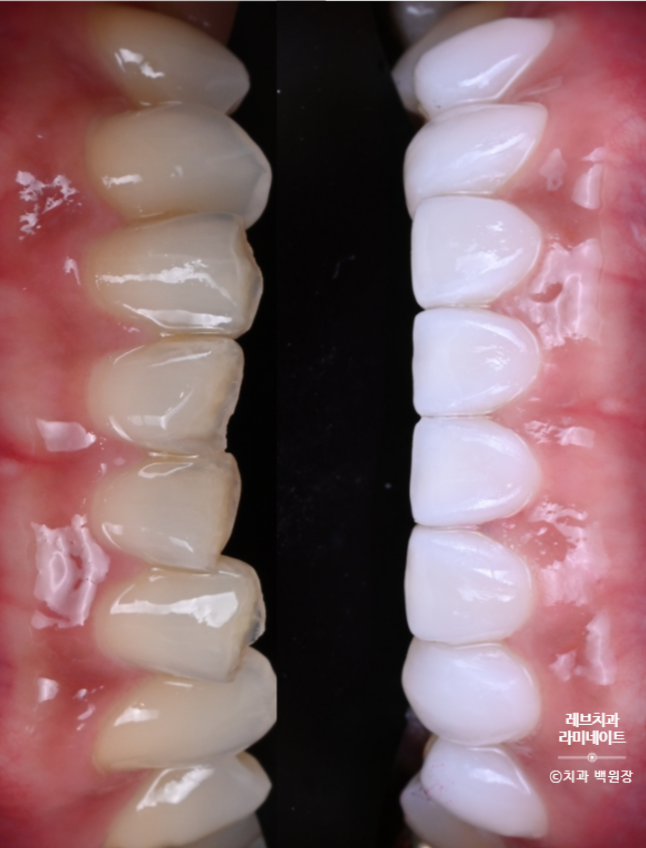

윗니와 아랫니의 색상차이를 확연히 구별하실 수 있겠죠?

위 치아는 라미네이트 치료가 되어 있으시지만, 아래 치아는 자연치 그대로입니다.

이렇게 보시면, 확실히 윗 치아와 아래 치아의 차이를 느끼실 수 있을거에요.

Before & After

약간의 잇몸성형을 통해 아랫니가 조금 더 보이게 함으로써 자연스러움을 추가하였습니다.

그리고 위 치아와 아래 치아 색상의 조화를 이루어 깔끔한 이미지를 가지실 수 있게 도와드렸습니다.

길이를 단정하게 맞추고, 색상을 개선하니 정말 20년은 젊어보이는 느낌이 들더라구요.